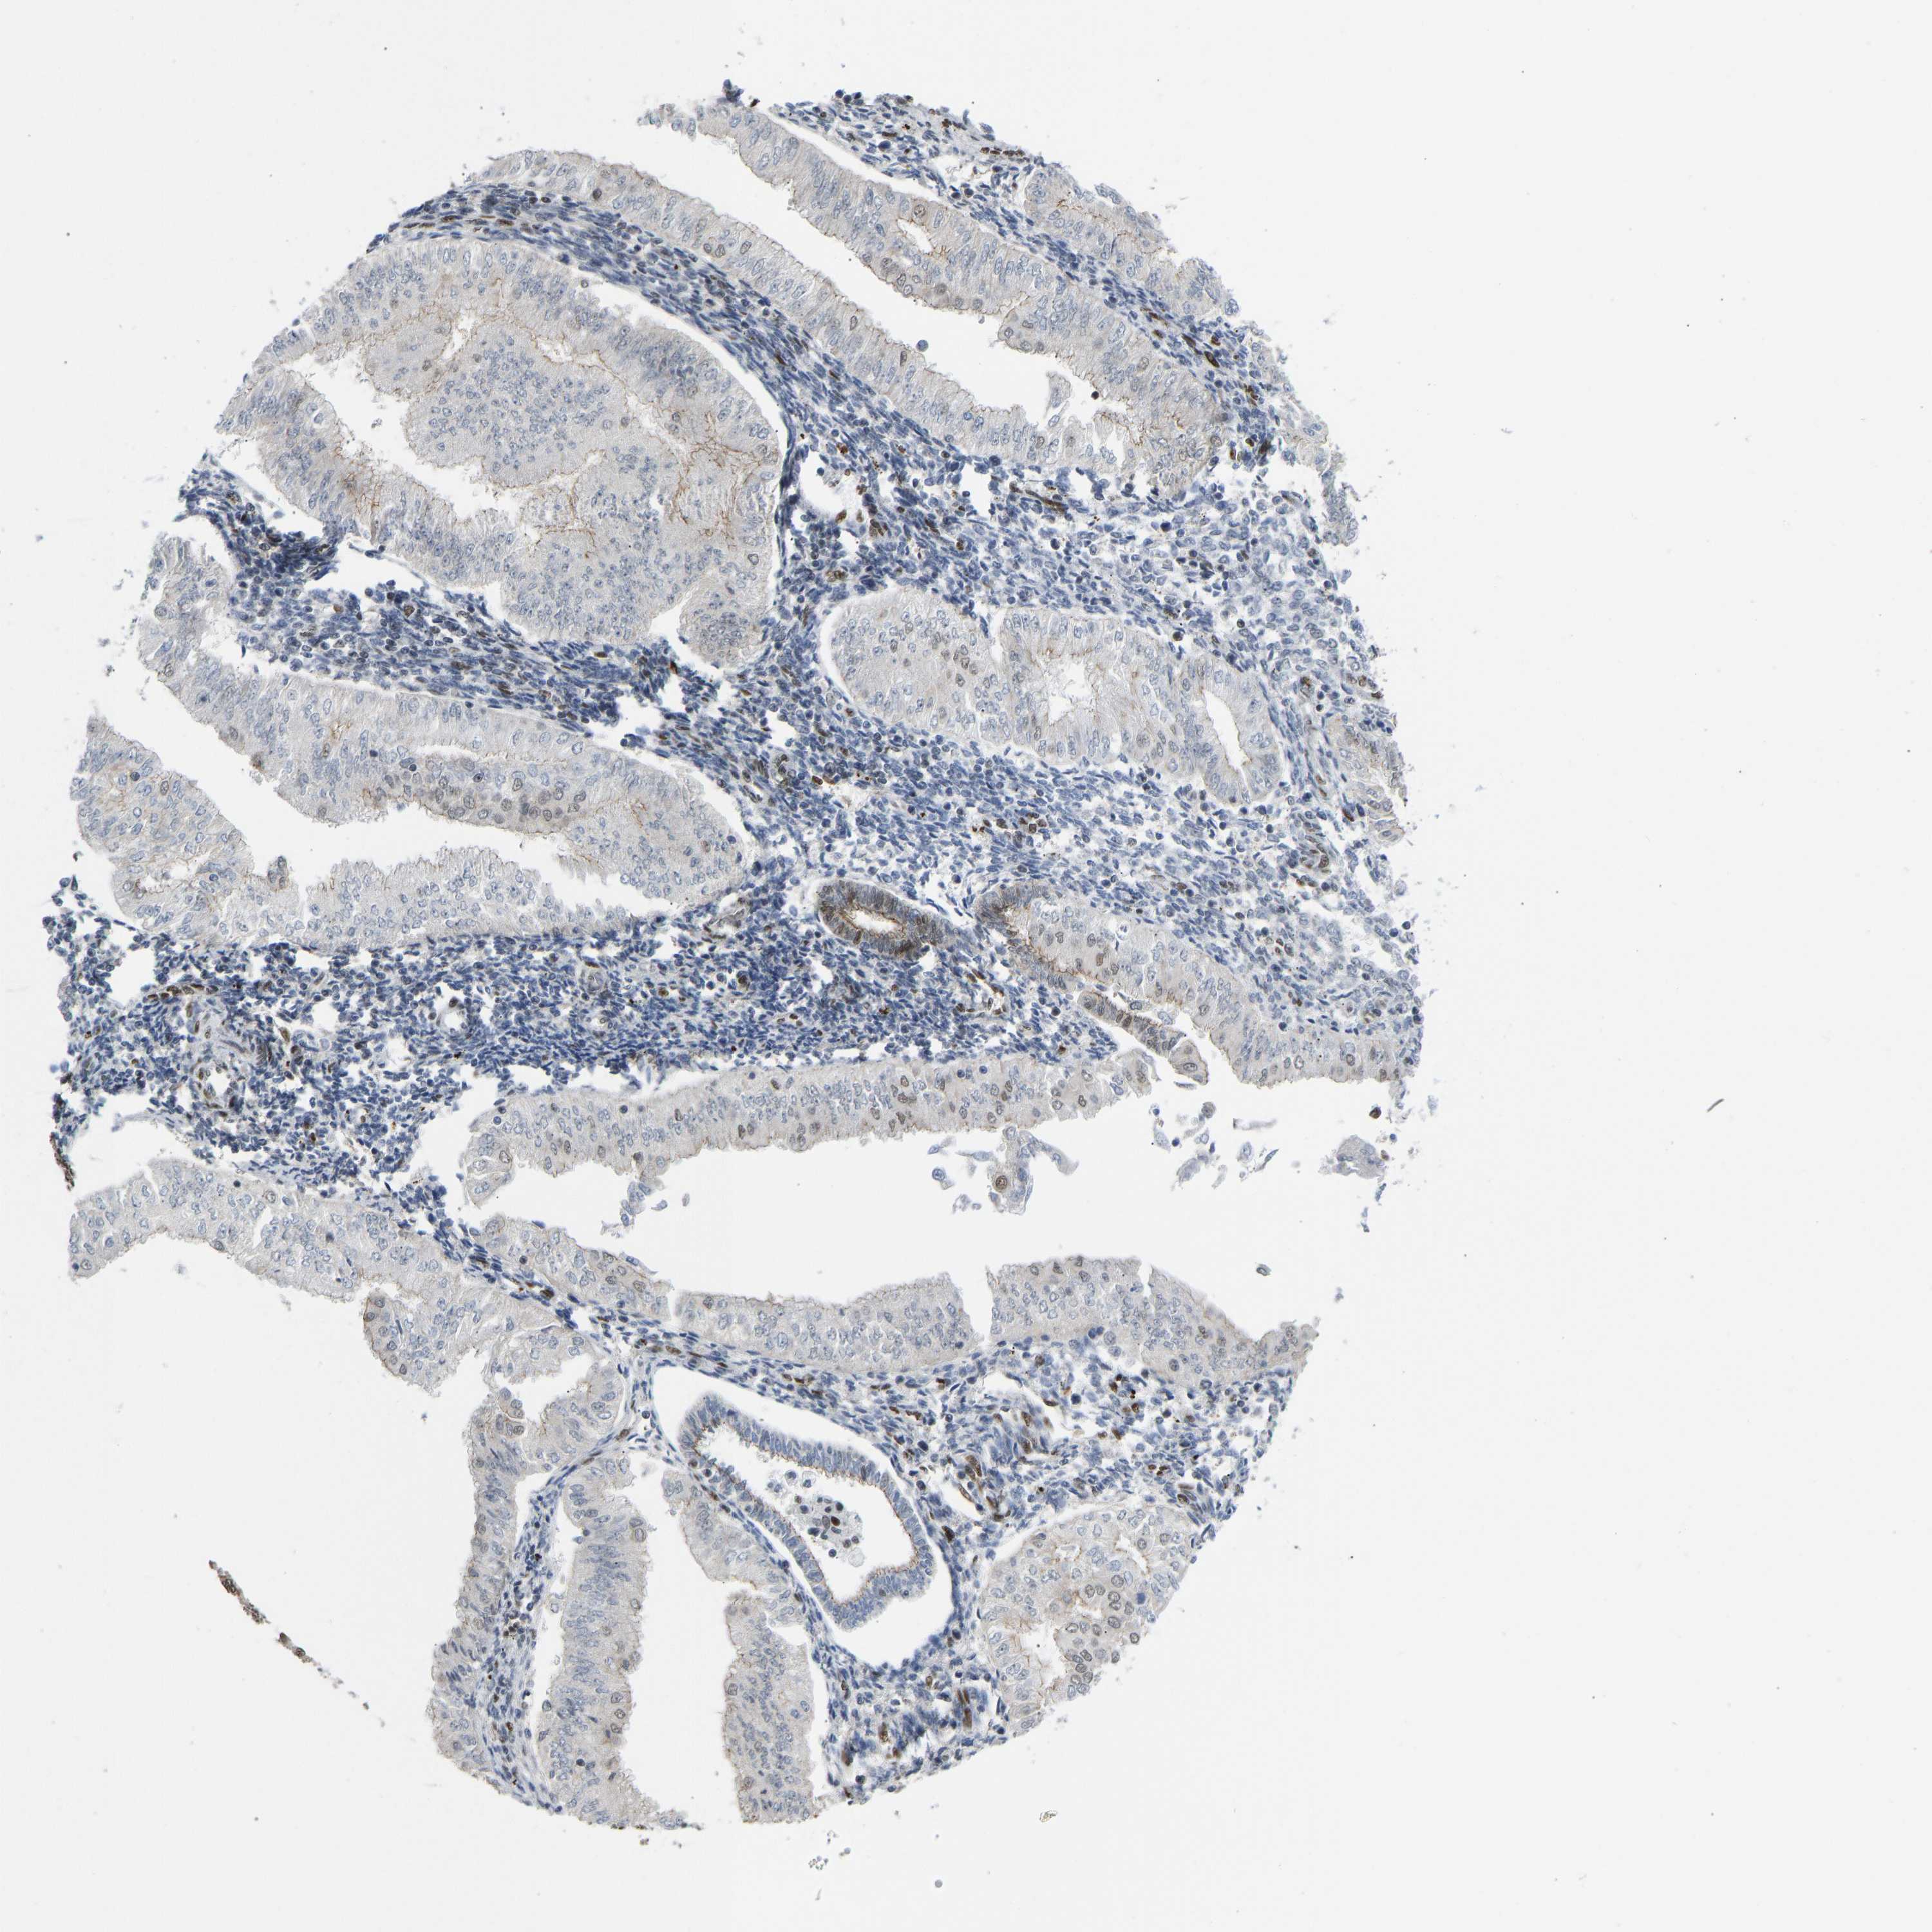

ENDOMETRIAL CANCER - Protein expressioni

A mouse-over function shows sample information and annotation data. Click on an image to view it in a full screen mode. Samples can be filtered based on level of antibody staining by selecting one or several of the following categories: high, medium, low and not detected. The assay and annotation is described here.

Note that samples used for immunohistochemistry by the Human Protein Atlas do not correspond to samples in the TCGA dataset.

Antibody stainingi

Antibody staining in the annotated cell types in the current human tissue is reported as not detected, low, medium, or high, based on conventional immunohistochemistry profiling in selected tissues. This score is based on the combination of the staining intensity and fraction of stained cells.

Each image is clickable and will lead to virtual microscopy that enables deeper exploration of all samples and also displays staining intensity scores, fraction scores and subcellular localization as well as patient and tissue information for each sample.

Antibody HPA017998

Antibody HPA018864

Staining

High

Medium

Low

Not detected

Intensity

Strong

Moderate

Weak

Negative

Quantity

>75%

75%-25%

<25%

None

Location

Nuclear

Cytoplasmic/membranous

Cytoplasmic/membranous,nuclear

Adenocarcinoma, NOS